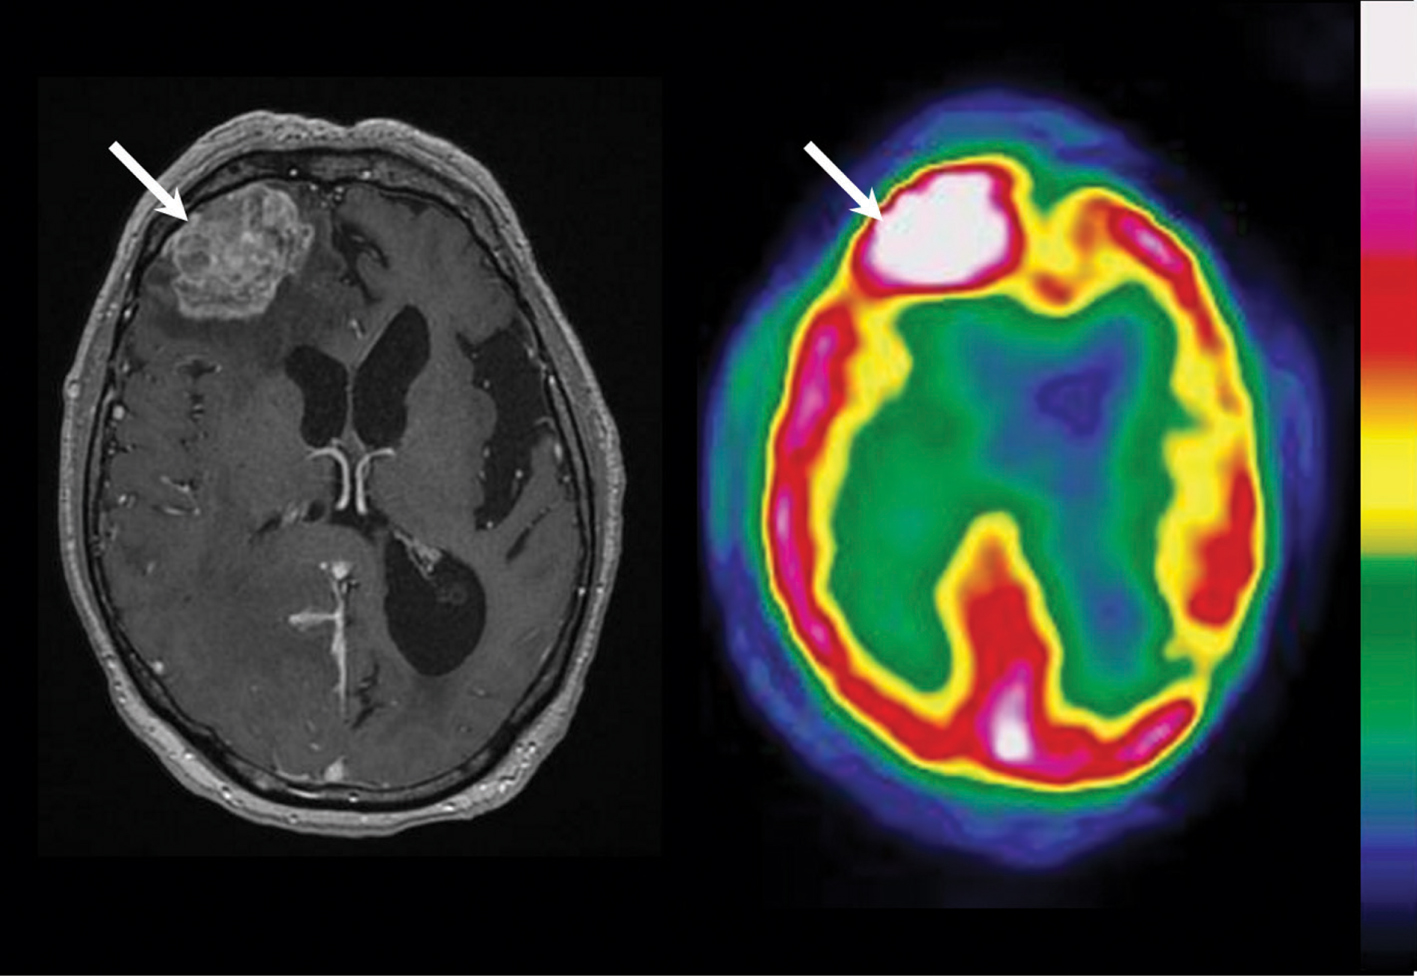

11C-MET is considered as very helpful in the assessment of these patients because the decrease in amino acid in the metabolically active tumor volume is a sign of treatment response associated with long-term outcome (83, 84). Accordingly, combined assessment with MRI and 11C-MET at 8 weeks can differentiate true responders, that is, those predicted to show a more favorable prognosis, from pseudoresponders (85). F18 labeled amino acid tracers can also determine treatment response after chemotherapy with a higher accuracy than MRI alone. A comparative illustration between 18F-FET PET and contrast-enhanced MRI is shown in Figure 3. For example, in a study involving 25 patients with glioblastoma after early completion of radiochemotherapy, a decrease in both 18F-FET TBR(max) and TBR(mean) was found to be a highly significant and independent statistical predictor of progression-free survival and overall survival. On the contrary, contrast enhancement volume changes had no significant predictive value for survival (86).

Fig 3

Figure 3 18FET-PET in a 59-year-old woman with glioblastoma. Brain imaging was performed after surgery (upper panel; MRI-/FET-1) and 6–8 weeks after completion of radiochemotherapy (lower panel; MRI-/FET-3). Contrast-enhanced MRI with corresponding contrast-enhanced volume is shown on the left and 18F-FET PET with corresponding metabolic volume on the right. Enlargement of contrast-enhanced volume on MRI 6–8 weeks after completion of radiochemotherapy (lower panel) is suggestive of tumor progression, whereas 18F-FET PET conversely indicates responsiveness with decreasing amino acid uptake (reduction of TBRmax) and unchanged metabolic volume. (Adapted from J Nucl Med 2012;53:1048–1057. Copyright: Society of Nuclear Medicine and Molecular Imaging, Inc. Reproduced with Permission.)